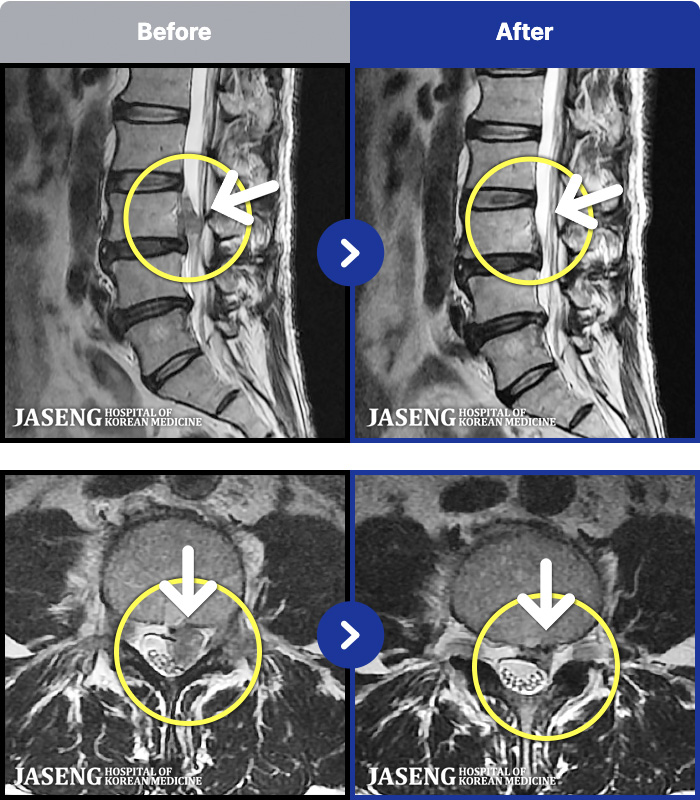

1,268 MRI ũ ʸ Ȯϼ.